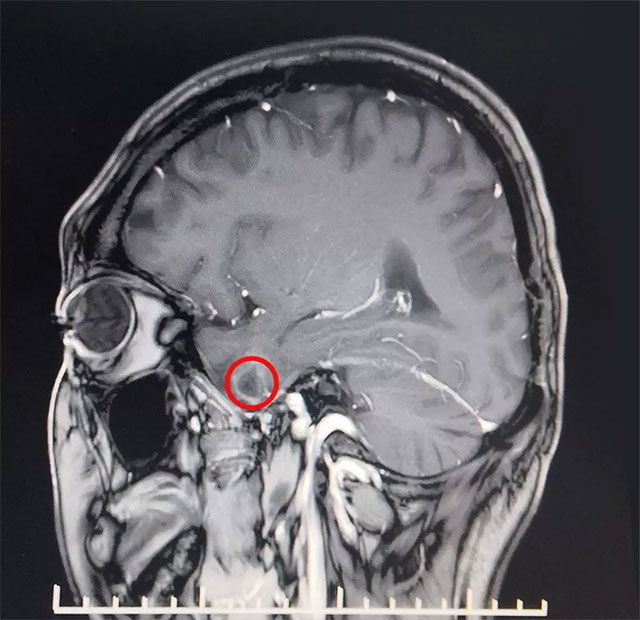

▲ 患者致癫灶位置

近期,上海蓝十字脑科医院功能神经外科收治了一名外伤继发性癫痫患者,通过综合运用磁共振、24小时长程视频脑电并结合临床病史等最终精准定位致癫灶,并成功为其手术切除。

患者王先生27岁,自13岁时首次发病,经过长期规律多种药物治疗效果不佳,期间严重时发作频率多达七次到八次每天,常于情绪激动、打牌及劳累时诱发,确诊为药物难治性癫痫。经过检查,MRS示双侧海马结构异常,左侧颞叶软化灶形成。VEEG检查可见异常波:左侧大脑明显异常,大量癫痫波,结合患者病史并综合相关检查最终确定癫痫病灶位于左侧颞叶、海马处。